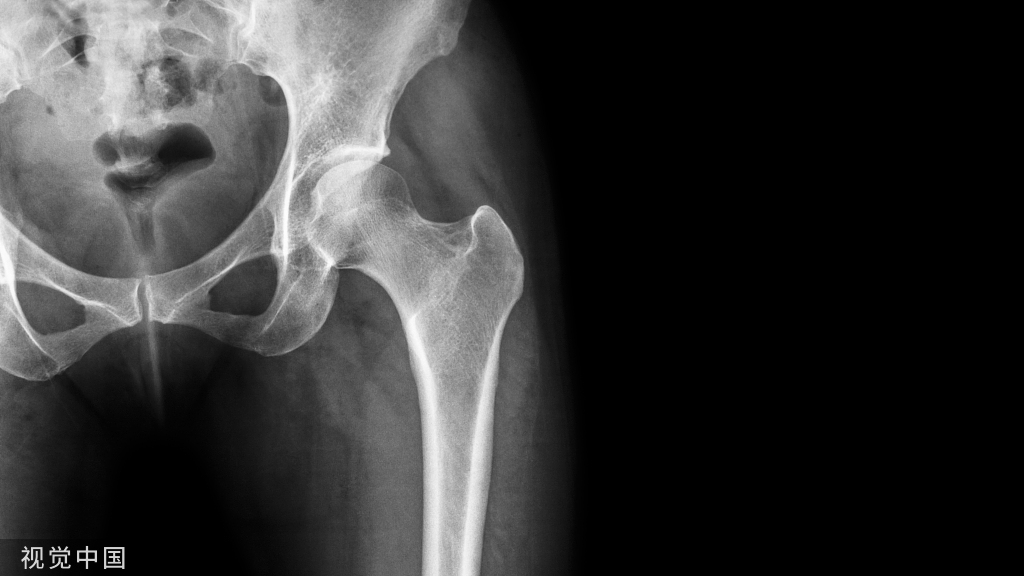

疲劳性骨折易发生部位及族群疲劳性骨折最容易发生的部位为下肢骨骼(胫骨、跗骨、跖骨、股骨、腓骨和种子骨),其次为腰椎、肋骨、肱骨、桡骨和尺骨。

若是位于较深处的构造,例如股骨,则疼痛可能会有扩散的情形;另外,虽然软组织肿胀的情形并不明显,特别是在活动之后有可能会发生。 通常运动时或运动后会感到疼痛,休息后,疼痛会消失或减缓;患者偶尔也会突然出现急性疼痛的情形。

一般而言,会使用X-ray、Bone scan、CT、MRI等影像判别技术协助确诊,而Bone scan(骨扫描)的准确性是当中最高的。

因临床上无典型的外伤史,早期X线平片通常为阴性,容易漏诊或误诊。